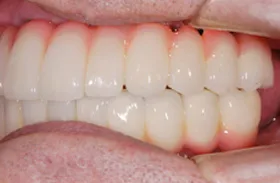

咀嚼障害のため来院されたケース(all-on-4)

60代 男性

咀嚼障害、歯茎の痛みを訴えられ、来院されました。

■治療前

■治療後

| 主訴 | かみにくい・全体的に歯茎が腫れて痛みがある 痛みがある |

| 治療方法 | 上下顎に複数本のインプラントを使用し、一体型の補綴物をセット |

| 治療期間 | 約1年 |

| 通院回数等 | 約20回 |

| 費用 | 約600万円 |

| リスク・副作用 | 補綴物が過度な力で破損するリスクがある |